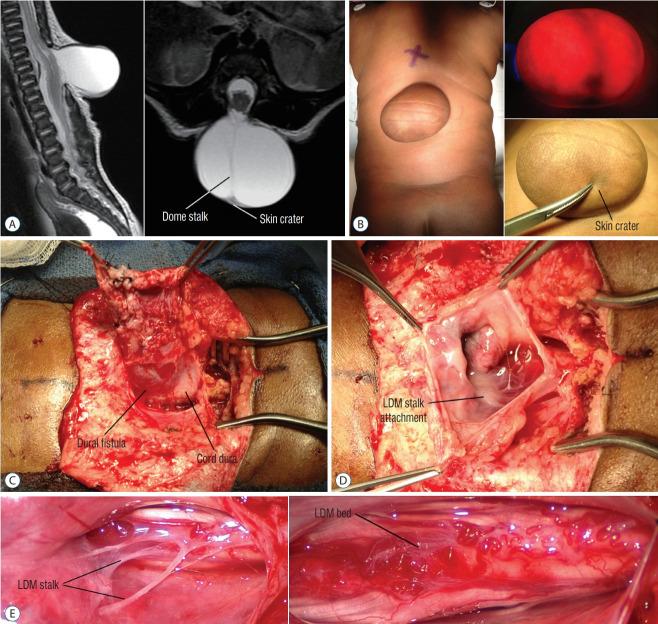

Spinal dysraphic lesions due to focal nondisjunction in primary neurulation are commonly encountered in paediatric neurosurgery, but the "fog-of-war" on these conditions was only gradually dispersed in the past 10 years by the works of the groups led by the senior author and Prof. Kyu-Chang Wang. It is now clear that limited dorsal myeloschisis and congenital spinal dermal sinus tract are conditions at the two ends of a spectrum; and mixed lesions of them with various configurations exist. This review article summarizes the current understanding of these conditions' embryogenetic mechanisms, pathological anatomy and clinical manifestations, and their management strategy and surgical techniques.

由于原发性神经管形成过程中的局灶性不分离导致的脊柱裂病变在小儿神经外科中很常见,但在过去10年中,由资深作者和王宇辰教授领导的团队的工作才逐渐驱散了这些病症上的“战争迷雾”。现在已经明确,有限性背侧脊髓裂和先天性脊柱皮样窦道是同一谱系两端的病症;并且存在各种形态的它们的混合病变。这篇综述文章总结了目前对这些病症的胚胎发生机制、病理解剖和临床表现,以及它们的治疗策略和手术技术的认识。